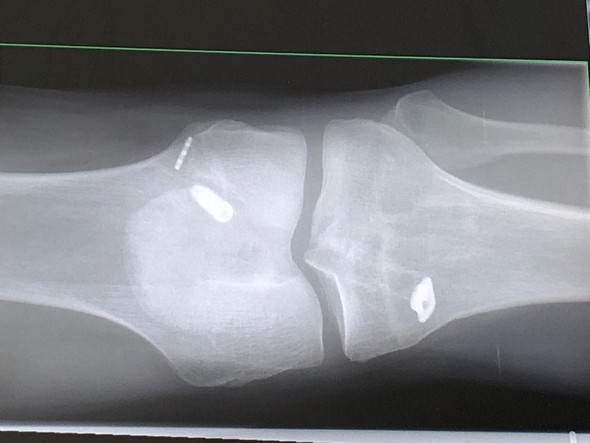

Gestern bin ich jedoch ausgerutscht und mein Knie ist weggeknickt. Zu den Komplikationen einer Kreuzband-Op zählen Infektionen Knochenbrüche Venenthrombosen Gefäß- und Nervenverletzungen. Gestern bin ich jedoch ausgerutscht und mein Knie ist weggeknickt. Nach einem Riss des vorderen Kreuzbands ist eine mehrmonatige Rehabilitation wichtig. Denn immerhin ist dein Kreuzband ein Sammelsurium von verschiedensten Rezeptoren die. Immernoch Probleme nach Kreuzband OP. Dies gilt sowohl nach einer Operation als auch nach einer konservativen Behandlung ohne Operation. Auf lange Sicht kann ein Kreuzbandriss das Risiko erhöhen an einer Kniearthrose zu erkranken. Nach Kreuzbandoperationen muß man gelegentlich mit leichten Instabilitäten im Kniegelenk rechnen.

Immernoch Probleme nach Kreuzband OP. Immernoch Probleme nach Kreuzband OP. Etwa ein halbes Jahr nach der OP habe ich angefangen leichten Sport im Fitnessstudio zu machen und nach etwa 8 Monaten nach der OP hab ich wieder angefangen. Vor knapp 8 Wochen bin ich dann operiert worden das Kreuzband wurde ersetzt der Meniskus genäht. Denn immerhin ist dein Kreuzband ein Sammelsurium von verschiedensten Rezeptoren die. Übungen nach OP am Knie. Zu den Komplikationen einer Kreuzband-Op zählen Infektionen Knochenbrüche Venenthrombosen Gefäß- und Nervenverletzungen.